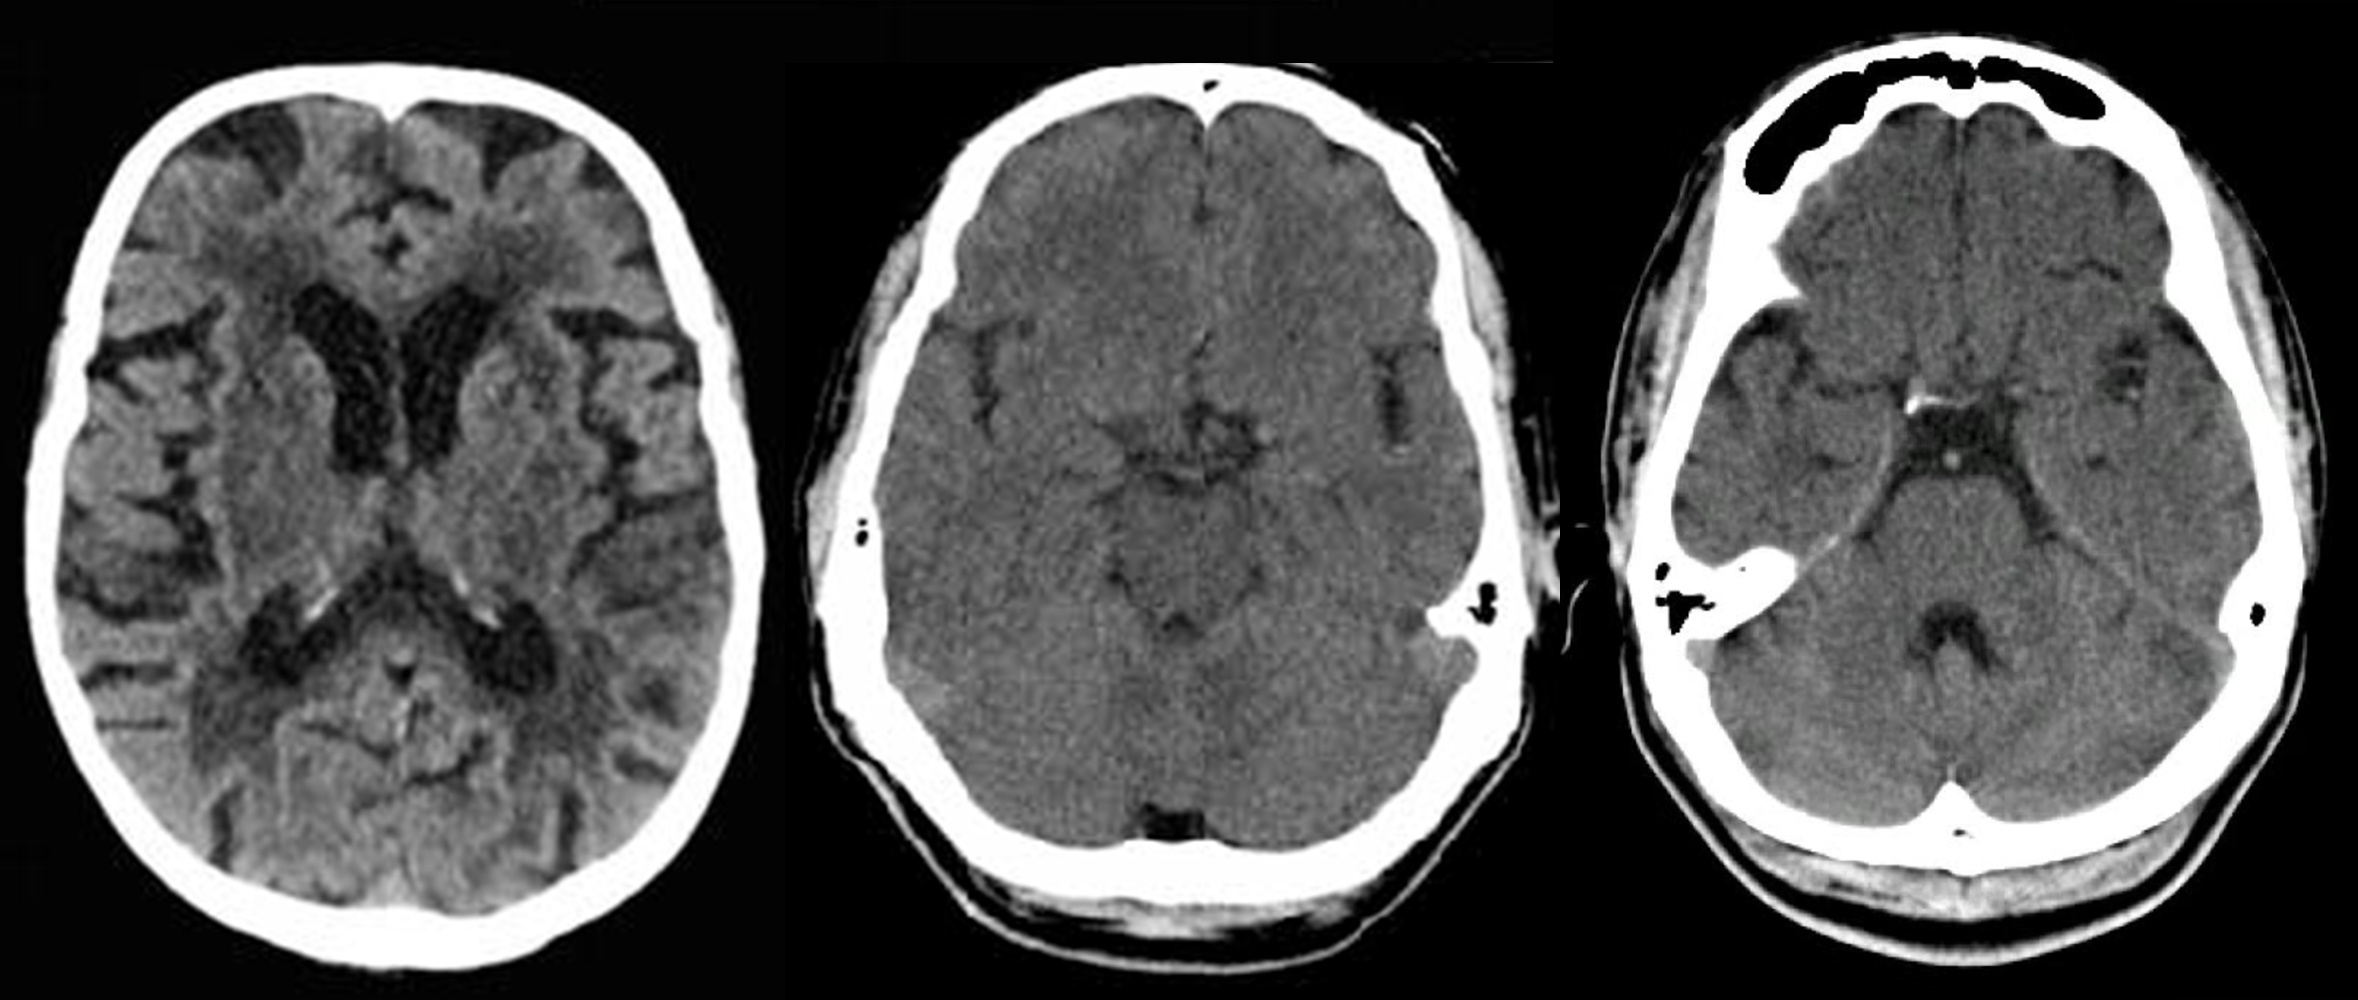

ASPECTS & PC-ASPECTS

ASPECT Score: Right Left